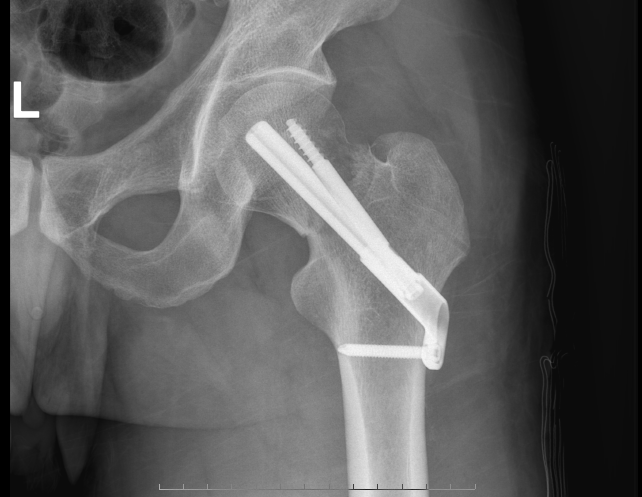

最近,家住洛溪的王阿姨不慎摔倒,自述髋部持续疼痛,无法动弹。随后在家人的陪同下到番禺区第二人民医院骨二科(创伤骨科)就诊,被诊断为右股骨颈骨折。股骨颈骨折属于髋部骨折,极易发生股骨头坏死,处理不当将严重影响患者的生活质量。王阿姨住入骨二科后,吴斌主任团队决定通过治疗股骨颈骨折微创新技术“FNS(股骨颈动力交叉钉系统)”,为王阿姨完成治疗。手术切口4cm,手术时间1个小时,出血量少;术后3天已经可以下床不负重活动了,手术效果让王阿姨及家人非常满意。术前影像资料:术后影像资料:为她主刀的吴斌主任介绍说:目前治疗股骨颈骨折,传统做法大致分为三类分别是:空心钉固定内固定、钢板螺钉固定以及关节置换。而“股骨颈动力交叉钉系统”,在番禺乃至广州尚属创新。FNS系统是目前国内外股骨颈骨折最新最前沿治疗方案。随访表明接受了“股骨颈动力交叉钉系统”治疗的患者,普遍反映恢复良好。吴斌主任还说到:FNS结合了空心钉和DSH的优势,具有微创、安全、稳定等一系列优点,有利于患者早期恢复,降低股骨头坏死几率。通过FNS技术,无论是骨折端的支撑稳定性还是角的旋转稳定性,均得到有效提升,同时不用置换关节就可以解决股骨颈骨折的问题,这是从治疗理念上的创新。这项治疗股骨颈骨折的前沿技术,给股骨颈骨折病人带来了福音。骨二科专家介绍 吴斌  骨二科(创伤骨科)主任骨外科副主任医师从事骨外科工作近20年。毕业于广东医科大学,曾到中山医科大学孙逸仙纪念医院骨外科进修。担任广东省医师协会骨科医师分会创伤骨科学组委员,广东省医学教育协会脊柱外科分会委员,广东省临床医学会足踝外科专业委员会委员,广东省基层医药创伤救治专委会委员,广东省康复医学会骨质疏松及相关疾病分会委员,广州市医师协会脊柱外科医师分会委员,番禺区医学会骨科分会委员。在国家级、省级医学期刊发表医学论文20余篇。擅长骨与关节损伤诊治。熟练开展骨盆、髋臼骨折切开、闭合复位内固定术及各种复杂四肢关节内骨折切开、闭合复位微创手术治疗。胸腰椎爆裂性骨折切开复位内固定,经皮椎弓根钉内固定术。骨质疏松性椎体压缩性骨折经皮穿刺椎体成形,后凸成形术。腰椎管狭窄症,腰椎间盘突出症、腰椎滑脱手术治疗及人工髖关节置换术。 骨二科专家门诊时间专家:吴斌副主任医师出诊时间:周四全天出诊地点:门诊大楼3楼创伤骨科门诊(骨科2号诊室)骨科门诊咨询电话:020-32653119

最近,家住洛溪的王阿姨不慎摔倒,自述髋部持续疼痛,无法动弹。随后在家人的陪同下到番禺区第二人民医院骨二科(创伤骨科)就诊,被诊断为右股骨颈骨折。股骨颈骨折属于髋部骨折,极易发生股骨头坏死,处理不当将严重影响患者的生活质量。王阿姨住入骨二科后,吴斌主任团队决定通过治疗股骨颈骨折微创新技术“FNS(股骨颈动力交叉钉系统)”,为王阿姨完成治疗。手术切口4cm,手术时间1个小时,出血量少;术后3天已经可以下床不负重活动了,手术效果让王阿姨及家人非常满意。 术前影像资料:  术后影像资料: 为她主刀的吴斌主任介绍说:目前治疗股骨颈骨折,传统做法大致分为三类分别是:空心钉固定内固定、钢板螺钉固定以及关节置换。而“股骨颈动力交叉钉系统”,在番禺乃至广州尚属创新。FNS系统是目前国内外股骨颈骨折最新最前沿治疗方案。随访表明接受了“股骨颈动力交叉钉系统”治疗的患者,普遍反映恢复良好。吴斌主任还说到:FNS结合了空心钉和DSH的优势,具有微创、安全、稳定等一系列优点,有利于患者早期恢复,降低股骨头坏死几率。通过FNS技术,无论是骨折端的支撑稳定性还是角的旋转稳定性,均得到有效提升,同时不用置换关节就可以解决股骨颈骨折的问题,这是从治疗理念上的创新。这项治疗股骨颈骨折的前沿技术,给股骨颈骨折病人带来了福音。 骨二科专家介绍  吴斌  骨二科(创伤骨科)主任骨外科副主任医师从事骨外科工作近20年。毕业于广东医科大学,曾到中山医科大学孙逸仙纪念医院骨外科进修。担任广东省医师协会骨科医师分会创伤骨科学组委员,广东省医学教育协会脊柱外科分会委员,广东省临床医学会足踝外科专业委员会委员,广东省基层医药创伤救治专委会委员,广东省康复医学会骨质疏松及相关疾病分会委员,广州市医师协会脊柱外科医师分会委员,番禺区医学会骨科分会委员。在国家级、省级医学期刊发表医学论文20余篇。擅长骨与关节损伤诊治。熟练开展骨盆、髋臼骨折切开、闭合复位内固定术及各种复杂四肢关节内骨折切开、闭合复位微创手术治疗。胸腰椎爆裂性骨折切开复位内固定,经皮椎弓根钉内固定术。骨质疏松性椎体压缩性骨折经皮穿刺椎体成形,后凸成形术。腰椎管狭窄症,腰椎间盘突出症、腰椎滑脱手术治疗及人工髖关节置换术。 骨二科专家门诊时间专家:吴斌副主任医师出诊时间:周四全天出诊地点:门诊大楼3楼创伤骨科门诊(骨科2号诊室)骨科门诊咨询电话:020-32653119